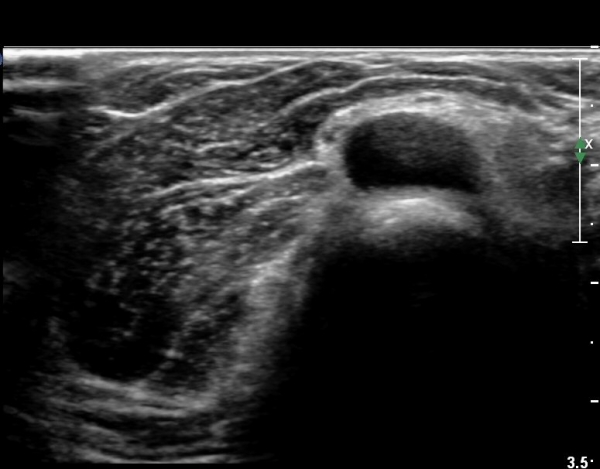

Á¶±Ý´õ ŽÃËÀÚ¸¦ ¸»´ÜÀ¸·Î À̵¿ÇÏ´Ï ³¶Á¾Àº ÀÛ¾ÆÁö°í ȸ¿Ü±Ù »çÀÌ¿¡ À§Ä¡ÇÏ´Â Èİñ°£ ½Å°æÀÇ

ºÎÁ¾ÀÌ °üÂûµÈ´Ù(»çÁø 6)

Èİñ°£ ½Å°æ Á¾´Ü¸é°Ë»ç¿¡¼­ ³¶Á¾¿¡ ÀÇÇÑ Èİñ°£ ½Å°æ ¾Ð¹Ú°ú  Èİñ°£ ½Å°æÀÇ ºÎÁ¾ÀÌ °üÂûµÈ´Ù(»çÁø 7).